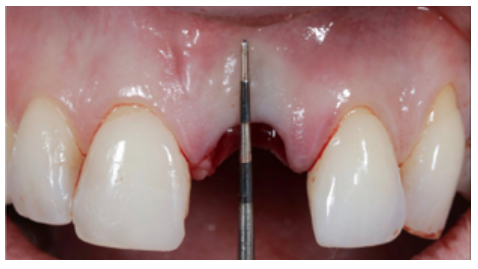

Clinical case: A 32-year-old female patient who attended for a possible root fracture of the upper left central incisor (ULCI), accompanied by a periodontal abscess at the bottom of the vestibule of the same tooth. A clinical and radiological examination established that the prognosis of the ULCI was unfavourable for conservative treatment. After evaluating the clinical features of the case, the treatment plan to extract the ULCI followed immediately by an osseointegrated implant (OII) and loading of a provisional prosthesis on the implant.

Conclusions: Rehabilitation on implants in situations of tooth loss in the aesthetic anterior sector, especially in young patients, requires a multidisciplinary treatment plan to extract the tooth and insert an OII in the correct 3-dimensional position. Various aspects need to be taken into account for this, particularly the residual remaining bone, the position of the gingival margin and preservation and conditioning of the peri-implant hard and soft tissues by means of grafts and proper handling of provisional prosthesis, until an ideal emergence profile and gingival contour is achieved before the final crown.

Different protocols have also been established for the management of the anterosuperior aesthetic sector, in addition to performing the immediate implant and provisional crown, including placing material between the OII and the buccal cortical to minimise possible collapse and the management of peri-implant soft tissue8-11.